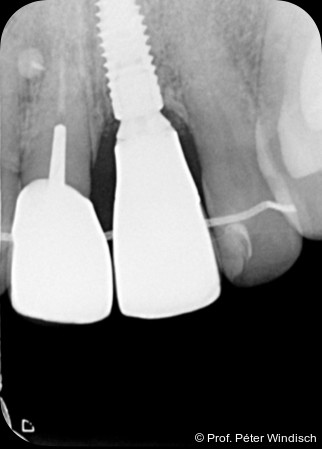

Radiologisch war ein signifikanter Knochenabbau um das Implantat zu verzeichnen (Abb. 2). Die klinische Untersuchung zeigte klassische Anzeichen einer periimplantären Entzündung: Bluten auf Sondieren (BOP+), erhöhte Sondierungstiefen (ST) und eine lokale Schwellung der Mukosa (Abb. 3–5). Das primäre Ziel war es, den Entzündungsprozess nicht chirurgisch zu stoppen und ein biologisches Milieu zu schaffen, das eine langfristige Stabilität ermöglicht. Der Implantataufbau wurde derzeit am Halsbereich zu dick ausgearbeitet und wies aus diesem Grund kein optimales Emergenzprofil auf. Nach der Eingliederung der definitiven prothetischen Versorgung kann es – insbesondere bei dicken suprakrestalen Weichgeweben – vorkommen, dass sich das Weichgewebe an die Kronenkontur adaptiert, was biologisch nicht immer gut toleriert wird. In der Folge kann es zu einer lokalen entzündlichen Reaktion kommen. Aus diesem Grund war zudem eine Umgestaltung der Krone vorgesehen.